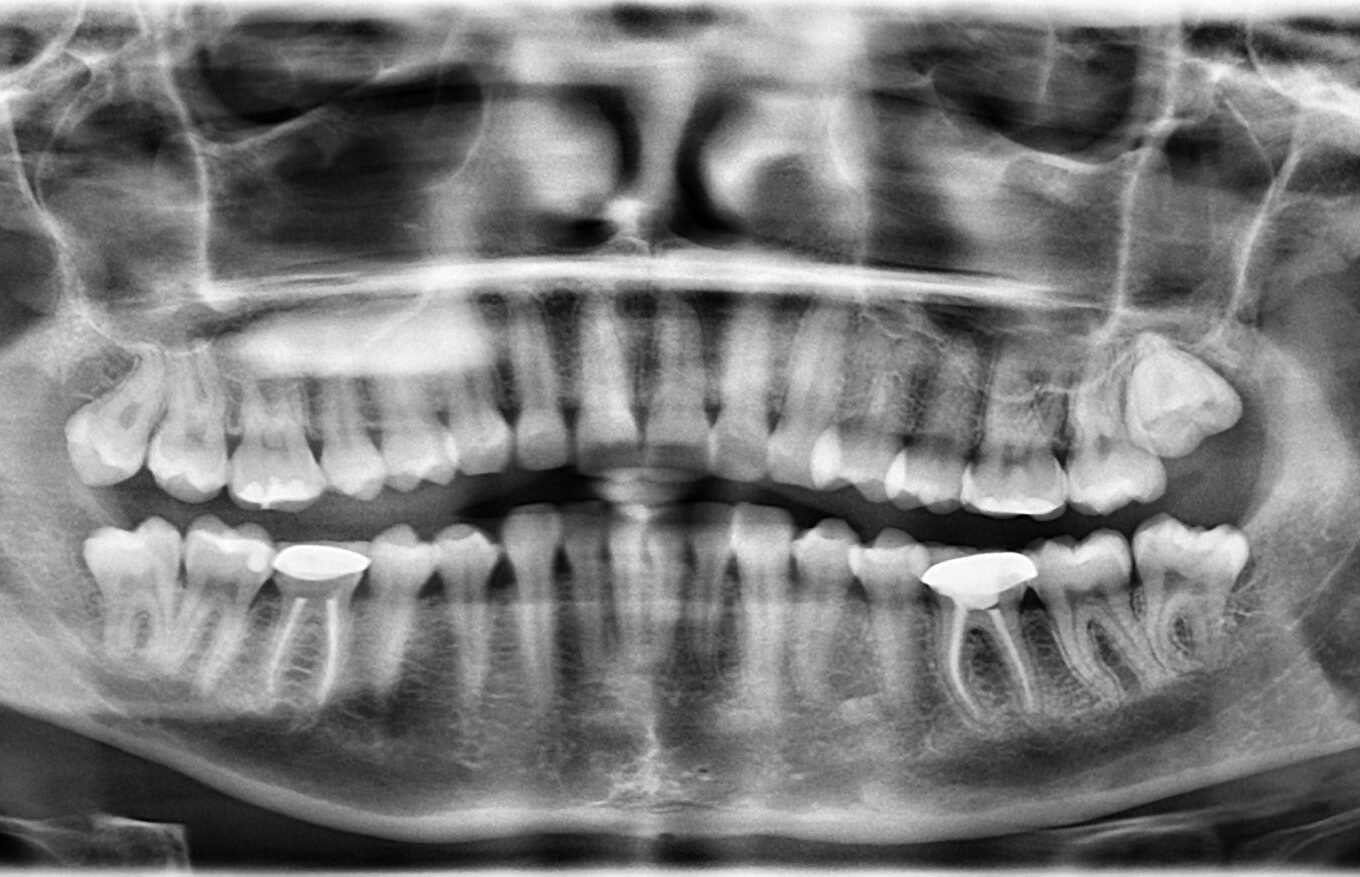

9. What option cannot be selected for this panoramic X ray?

10. What options cannot be selected for the upper jaw of this panoramic X ray?

11. What options cannot be selected for the lower jaw of this panoramic X ray?

12. What option cannot be selected for this panoramic X ray?

13. What option cannot be selected for this panoramic X ray?

14. What option cannot be selected for this Panoramic X ray?